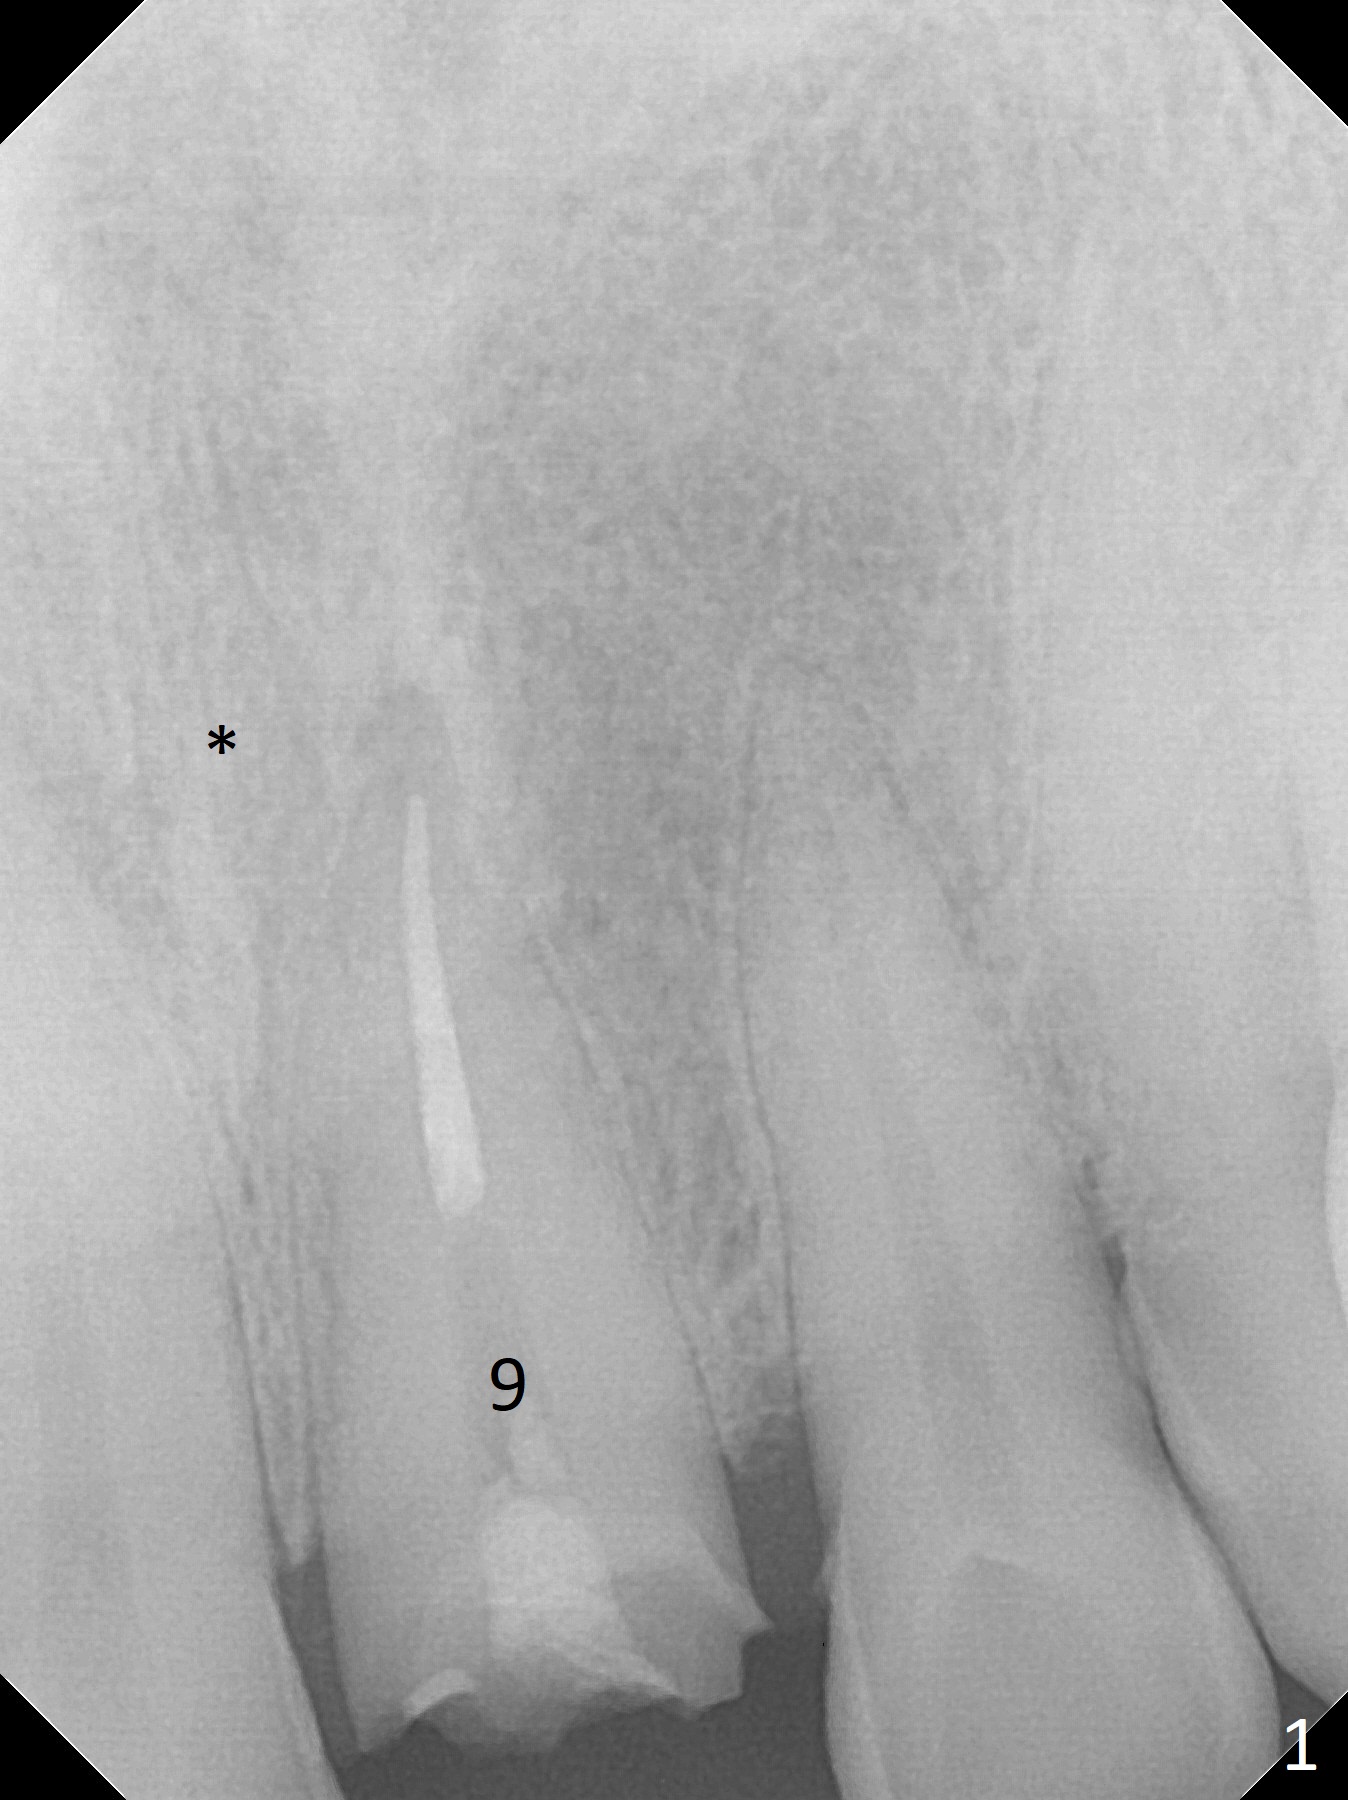

After breaking and dislodging the crown at #9, a 57-year-old man fractures the tooth (Fig.1). The teeth # 3 and 19 have cusp fracture or severe wear, indication for crowns. Since there is anterior deep bite, the implant should be long for primary stability (Fig.2). To avoid the Incisive Canal (*), start osteotomy distal. The initial depth will be 21 mm. After trying a 3.8x15 mm dummy implant with good trajectory, increase the osteotomy for larger implant (4.0 or 4.5 mm) to reduce chance of implant breakage due to heavy mastication.